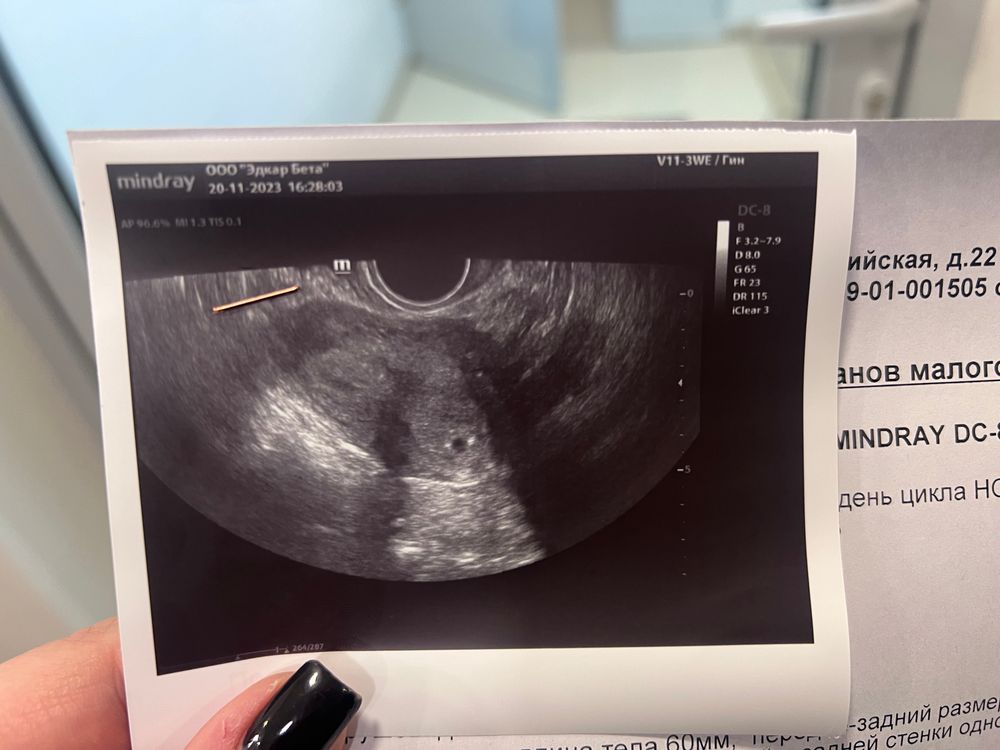

Первое узи🙏🏻🥹